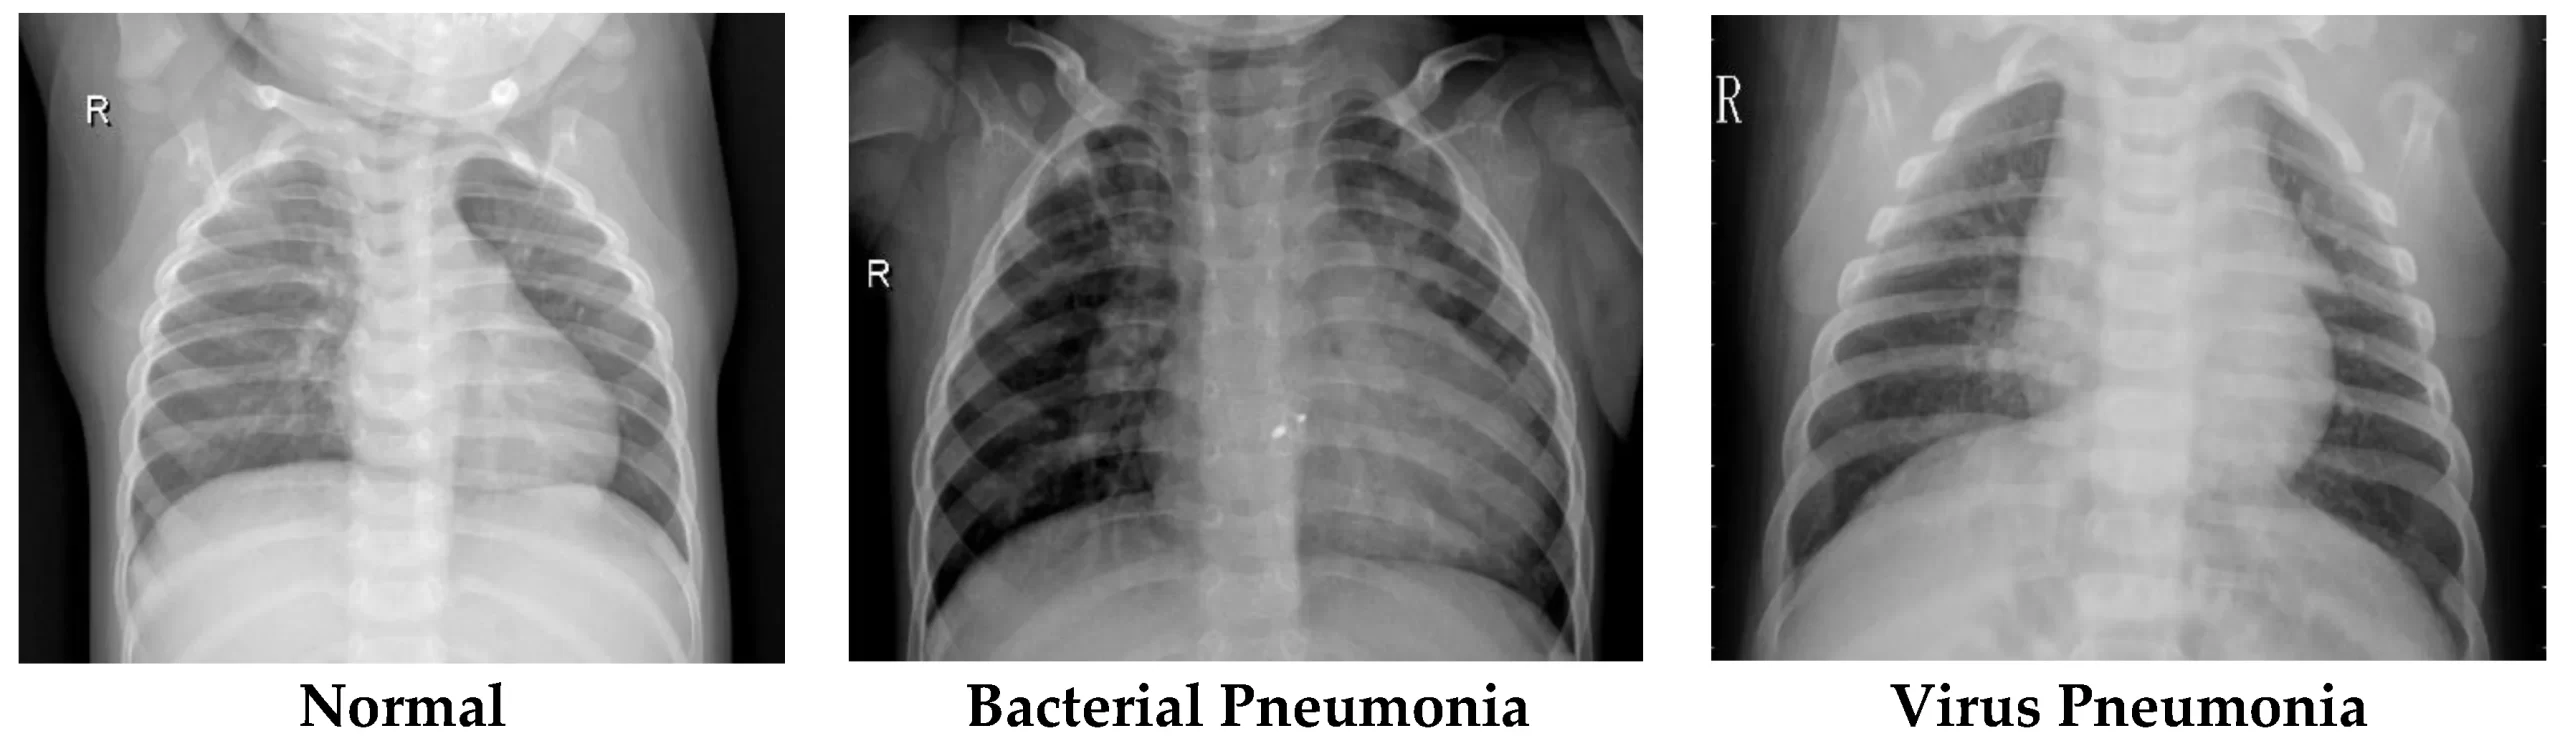

- تاباندن اشعه ایکس به قفسه سینه: این روش به پزشک شما کمک می کند تا ذاتالریه را تشخیص داده و میزان و محل عفونت را تعیین کند. با این حال، نمی تواند به پزشک شما بگوید که چه نوع میکروبی باعث ذات الریه شده است.